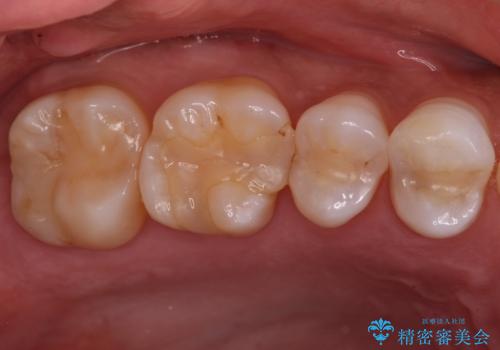

銀が目立つので白くしたい

担当医 青山卓弘